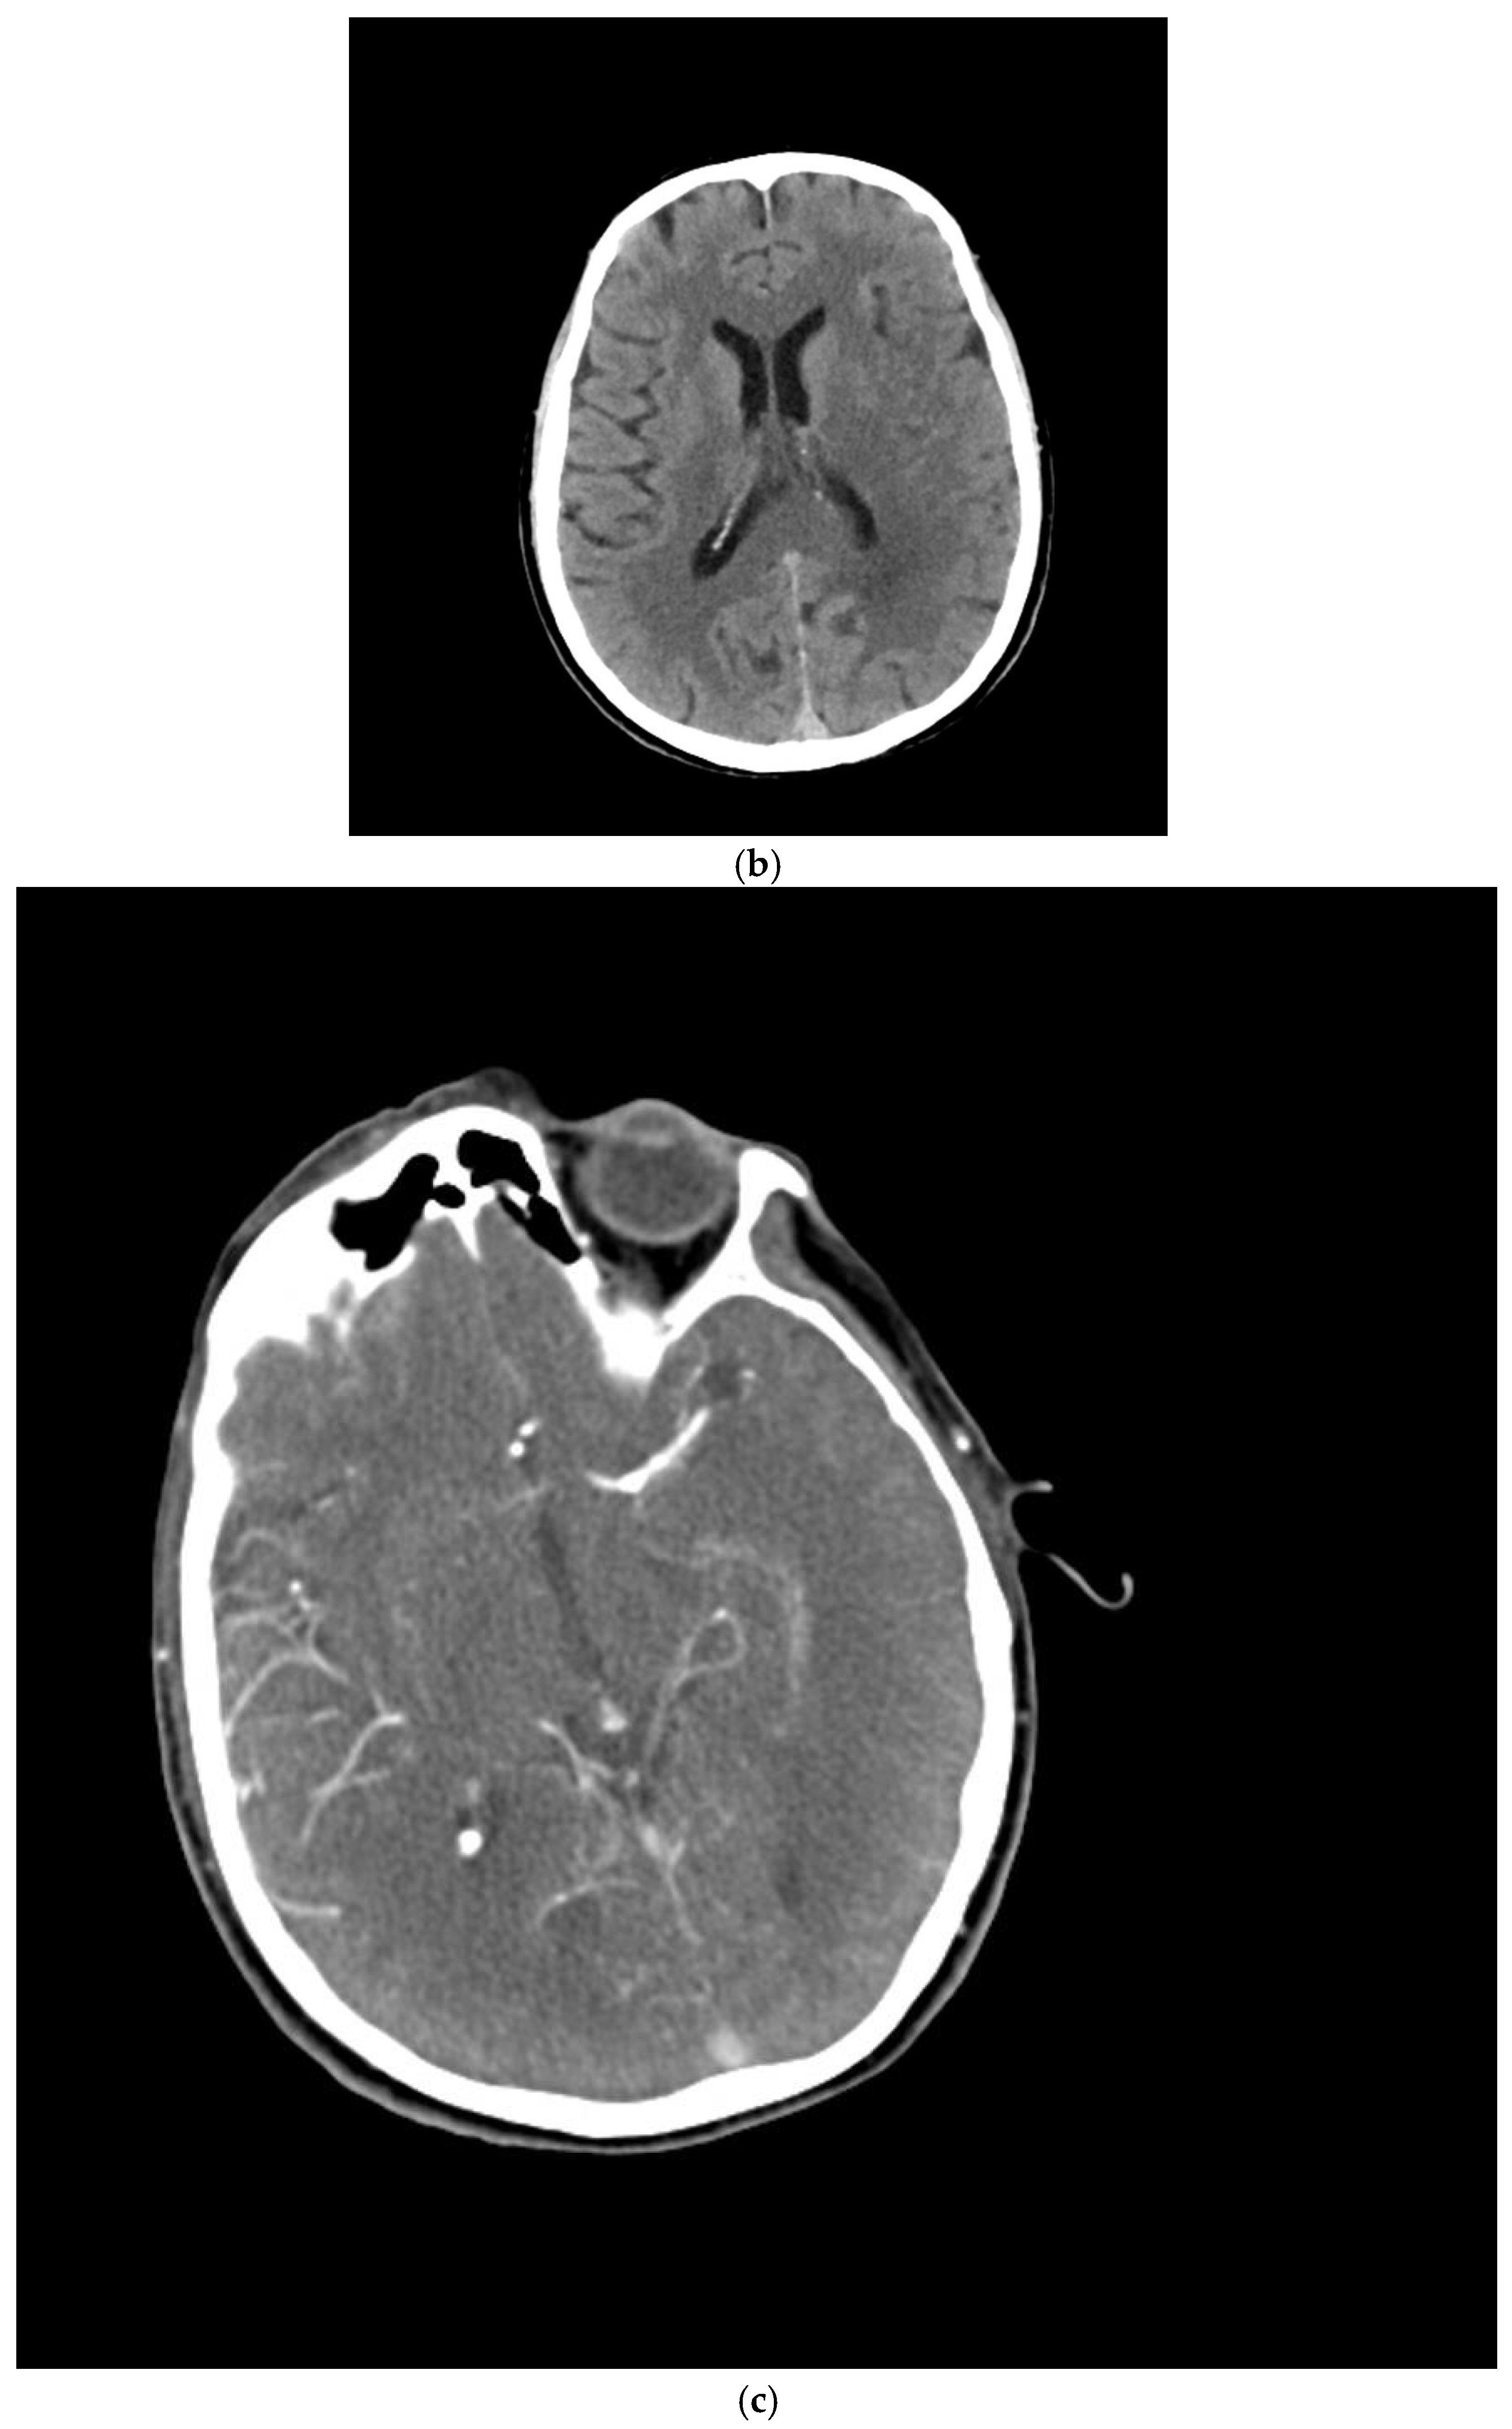

2.4. Imaging Protocol

| Occlusion Location | |

| MCA M1 | 37 (64.9%) |

| ICA terminal | 11 (19.3%) |

| ICA proximal | 17 (29.8%) |

| ACA | 5 (8.8%) |

| Basilar artery | 2 (3.5%) |

| Embolectomy Technique | |

| Aspiration | 22 (39.6%) |

| Aspiration and stent implantation | 35 (61.4%) |